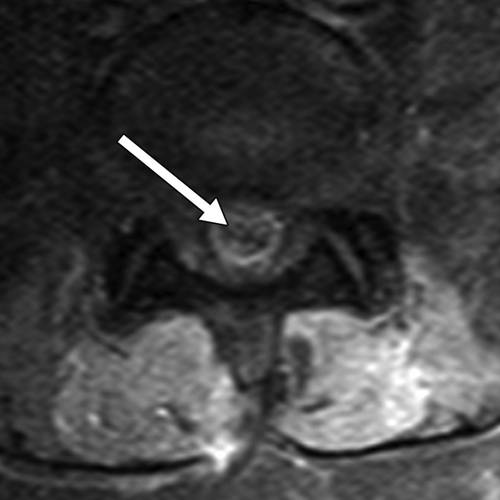

![]()

图14A-在L4-L5腰椎融合后2周,48岁的男性复发性左侧放射性疼痛。轴向T2加权MR图像显示与硬膜囊后部相邻的积液(箭头)。